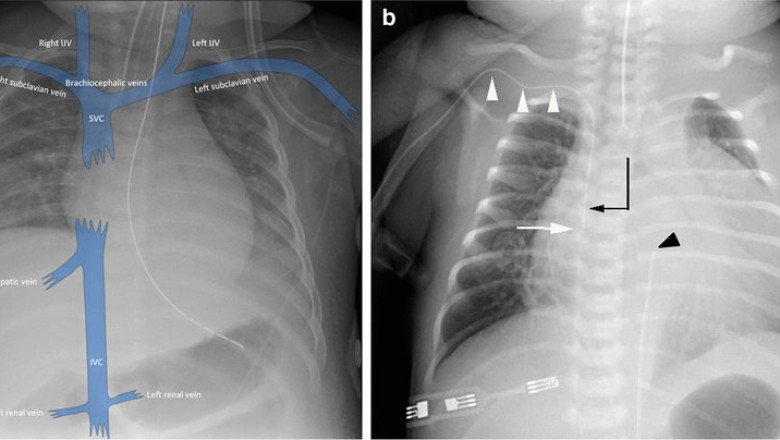

A Central Venous Catheter (CVC) is a medical device that is used to deliver medications, nutrition, fluids, or blood products directly into the bloodstream. It is inserted into a large vein in the chest or neck, and it is commonly used in critically ill patients who require long-term intravenous therapy or who have poor peripheral venous access. While CVCs are associated with some risks and complications, they are generally considered safe and effective when used appropriately by trained healthcare professionals.

Werner Frossman, a German physician, initially conducted central venous catheterization in 1929 by inserting a ureteric catheter into his antecubital vein. The catheter was subsequently inserted into his right ventricle using fluoroscopy, thus he proceeded to walk to the radiography department. Central Venous Catheter access has since evolved into a cornerstone of contemporary clinical treatment. Patients with these catheters will be encountered by clinicians from the majority of medical specialties. More than 15% of patients may experience a catheter-related problem despite the advantages central venous lines have for patients and doctors.